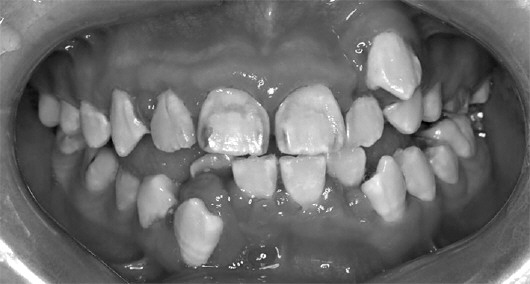

二、临床表现

本病好发于前牙唇侧的龈乳头和龈缘。唇侧牙龈肿胀较明显,龈乳头常呈球状突起,颜色暗红或鲜红,光亮,质地软,探诊出血明显。龈沟可加深形成龈袋,但附着水平无变化,亦无牙槽骨吸收。患者的主诉症状常为刷牙或咬硬物时出血、口臭等。

治疗后四个月